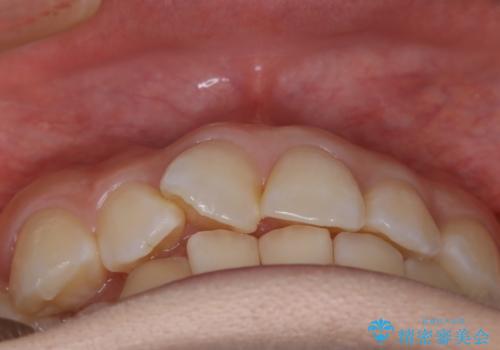

- 前歯のガタつきを主訴に来院されました。

生まれつき下の前歯が1本少なく、その分のスペースを上の前歯がガタつくことで埋めているという状況でした。

上下それぞれのガタつきをとっていく過程で、歯1本分のスペースの差を、上顎の前歯のIPRで調整して並べる方法をご提案させていただきました。

稀に、乳歯が抜けてもその後に永久歯が生えてこないことがあります。生まれつき歯の元となる「歯胚」というものが欠如していることが原因で本数が少なくなることを「先天欠如」といいます。

こういったケースの治療では欠損している歯の本数分反対の顎の歯(上顎に欠損がある場合は下顎の歯)を抜歯してスペースの調整をする場合や、欠損歯の幅分のIPRを反対の顎の歯に設定することでスペースのコントロールをするという方法、欠損している歯の分のスペースを残して矯正を終了し最後にブリッジ治療やインプラントで歯の本数を増やすという方法があり、状況や患者さんの希望により選択をしていきます。